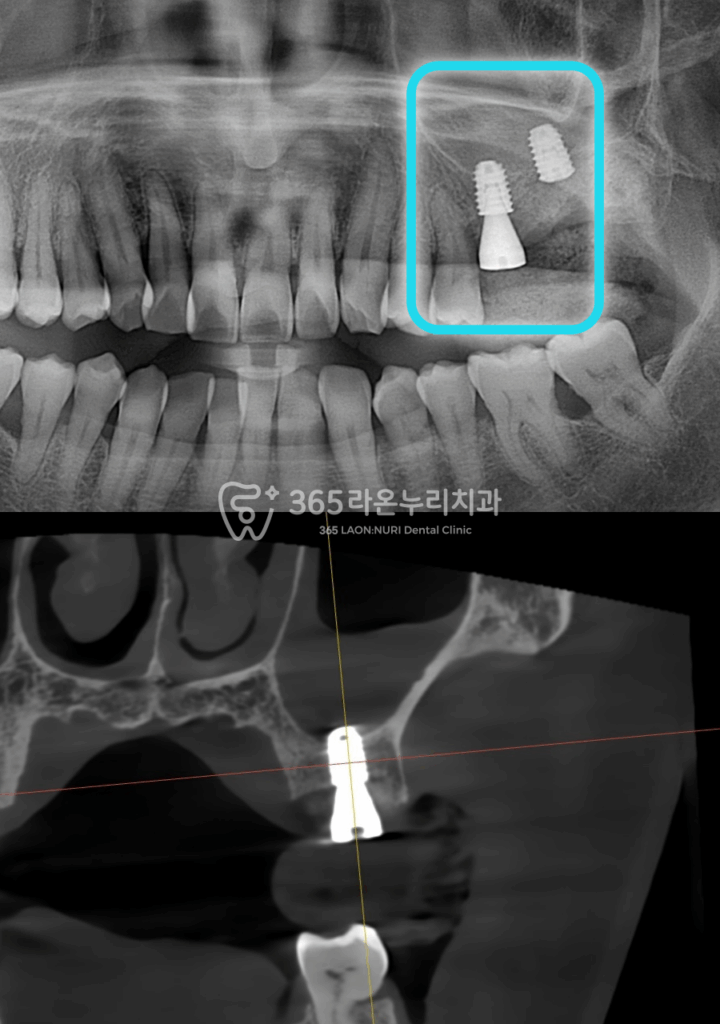

2025.4.13

세교동 치과 에서

식립된 모습을 확인해 보면

상악동쪽 뼈가 들어가

안전하게 식립된 모습을 볼 수 있습니다.